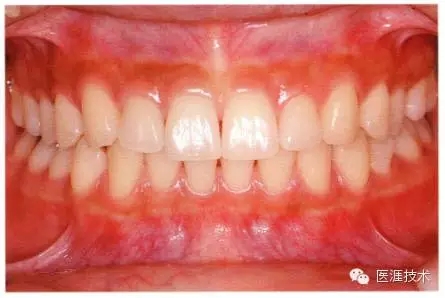

圖為28歲女性,無特殊全身疾病,不抽煙。10年前來院就診保養(yǎng)3年,期間中斷過,現(xiàn)又開始。齲壞風(fēng)險(xiǎn)高,當(dāng)初初診時(shí)已有好幾顆牙的鄰面有填充物,再填充了3牙的鄰面齲,現(xiàn)牙周組織健康。